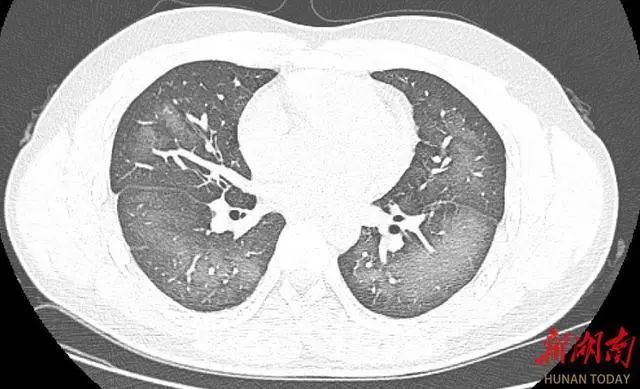

经检查,肺部CT片显示,李林双肺赫然呈现大范围白色样病变,报告提示“白肺”。

“白肺”一般是指重症肺炎在X线或CT检查下的表现,患者肺部呈现一大片的白色状态,往往会出现呼吸困难、呼吸衰竭,严重者还会出现其他脏器功能障碍。“白肺”常见于高龄(65岁以上)、免疫力低下、有重要器官慢性病史(如心脏病、中风史、慢性肾脏病、慢性阻塞性肺疾病等)、有多种疾病并存(比如既有高血压、糖尿病,又有心脏病、肺病、肾功能不全)等人群。